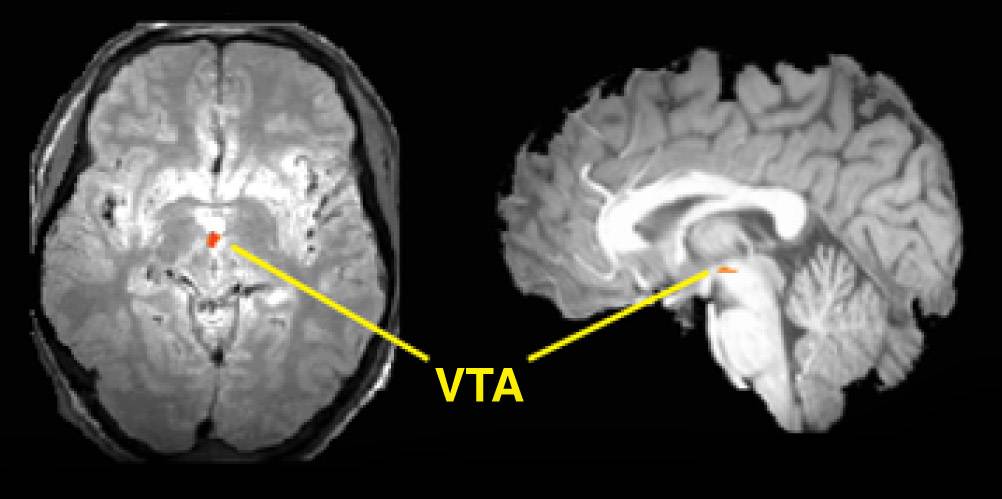

Horizontal (left) and vertical (right) slices of brain show increased blood flow (red region) in brainstem (VTA or ventral tegmental area) in measurements made by functional magnetic resonance imaging.

Reporting in the Feb. 28 edition of Science, the scientists describe using functional magnetic resonance imaging to study brainstem activity in dehydrated humans. The scanning technique allows researchers to watch the brain in action.

The team was able to develop high-resolution images that tracked the activity of tiny clusters of dopamine neurons. They weeded out distortions caused by many pulsing blood vessels in the brainstem. They also employed computerized rules of thumb known as algorithms and imaging techniques to reduce the effects of head movement and combine images from different subjects.

The MRI device produces three-dimensional images that show what portions of the brain engage during actions and thought processes. This allows the investigators to correlate physical processes with mental activities with unprecedented precision.

The brainstem, a tiny, root-shaped structure, is the lower part of the brain and sits atop the spinal cord. The area controls brain functions necessary for survival, such as breathing, digestion, heart rate, blood pressure and arousal. The brain structure also serves as the home base for the brain chemicals, also known as neuromodulators, such as dopamine, serotonin and norepinephrine. The chemicals spring forth into other brain regions from there, zipping along routes called axons.